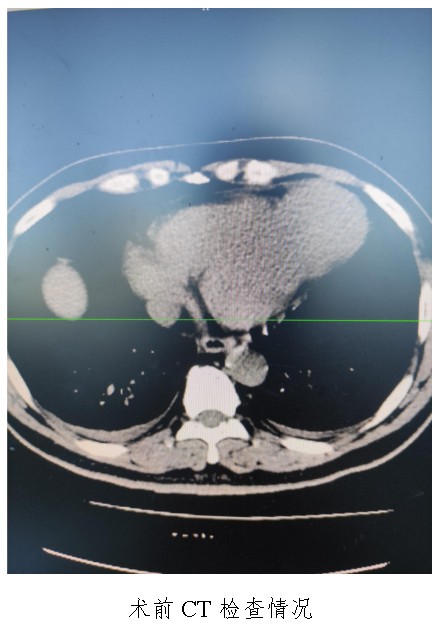

通訊員廖金文報道:一名50歲左心室前壁中下段及心尖部巨大室壁瘤患者在衡陽市中心醫(yī)院心胸外科廖金文主任、屈云劍副主任團(tuán)隊(duì)的精心治療下,接受左心室室壁瘤切除加左心室修補(bǔ)成型手術(shù)后,恢復(fù)良好,于11月1日出院。

10月18日,50歲的孟先生因反復(fù)胸悶氣促一周,夜間不能平臥來衡陽市中心醫(yī)院心胸外科就診,經(jīng)心臟超聲檢查提示左心室前壁中下段及心尖部巨大室壁瘤,66×57mm,最薄處約3mm?;颊哂卸嗄晏悄虿〔∈?,既往有無癥狀心肌梗死病史,曾行PCI治療。入科后,廖金文主任、屈云劍副主任組織心內(nèi)、麻醉、體外循環(huán)、重癥醫(yī)學(xué)科對病人病情進(jìn)行了多學(xué)科討論,一致認(rèn)為手術(shù)是治療該病例的唯一手段。經(jīng)過充分的術(shù)前準(zhǔn)備,10月24日,心臟外科團(tuán)隊(duì)給患者實(shí)施了左心室室壁瘤切除加左心室修補(bǔ)成型手術(shù),手術(shù)順利,術(shù)后經(jīng)過精心的治療管理,患者恢復(fù)良好,康復(fù)出院。該病例的手術(shù)成功,不僅是術(shù)中及手術(shù)團(tuán)隊(duì)智慧的結(jié)晶,也是多學(xué)科合作的結(jié)果,展示了衡陽市中心醫(yī)院處理復(fù)雜危重患者的能力。